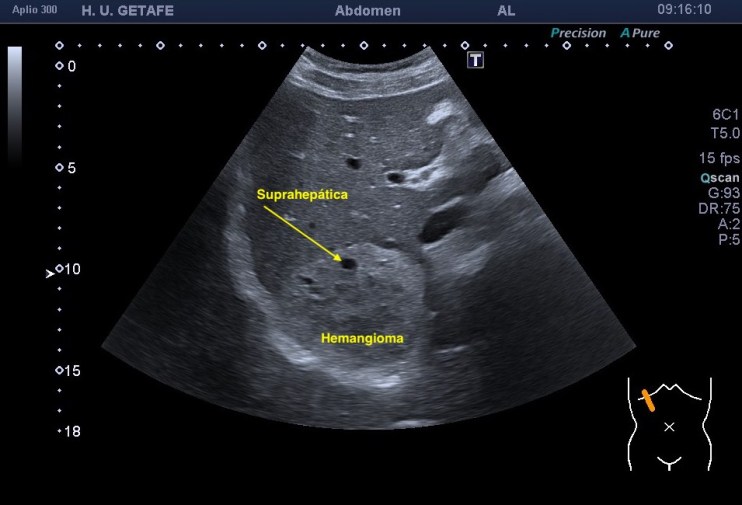

Te dejo las imágenes, estúdialas, luego las comento:

Bien, en el caso de hoy te presento un hemangioma atípico. Es hiperecogénico, pero su tamaño excede por tres el tamaño máximo de estas piezas patológicas ocupantes de espacio en el hígado. Está en torno a los 9 centímetros. Ligeramente heterogéneo este hemangioma es muy bonito porque rodea a una de las ramas de las suprahepáticas, como puedes ver en la imagen 1 y 2, en el corte axial se observa perfectamente.

El caso en si mismo no tiene gran relevancia a no ser que la sospecha fuese que la masa que sabemos que es de un hemangioma atípico fuera de otra índole, pero ¿cómo podríamos sospechar que una LOE es maligna? Bien, hay varias maneras, hoy te quiero explicar una que estas imágenes cuentan muy bien. Cuando una lesión ocupante de espacio o LOE es de sospecha maligna, se puede reconocer por la relación que mantiene con los vasos de la región que está ocupando. En este caso puedes ver perfectamente que la LOE está coexistiendo perfectamente con la rama de la suprahepática a la que está envolviendo, abrazando, pero sin desplazarla, sin agredirla, sin infiltrarla, es decir, la está respetando. Le permite el normal flujo de la sangre a través de ella (imagen 3), no la ocluye ni la tapona y la pared del vaso está respetada. Por tanto, esta lesión que por su tamaño y aspecto podría ser sospechosa (imagen 4 y 5), se torna amable al ver que respeta al vaso que toca.